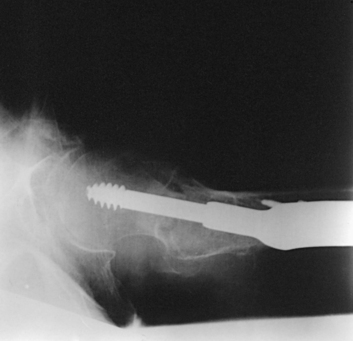

Structures shown: The resulting image shows an axiolateral projection of the femoral heads, necks, and trochanteric areas (Fig. 7-28).

Fig. 7-28 Axiolateral femoral necks: Cleaves method. A, Bilateral examination. B and C, Unilateral hip examination of a patient who fell. No fractures were seen on initial AP hip radiograph (B), and a second projection using the Cleaves method was performed. Chip fracture of femoral head (arrow) was seen (C). At least two projections are required in trauma diagnoses.